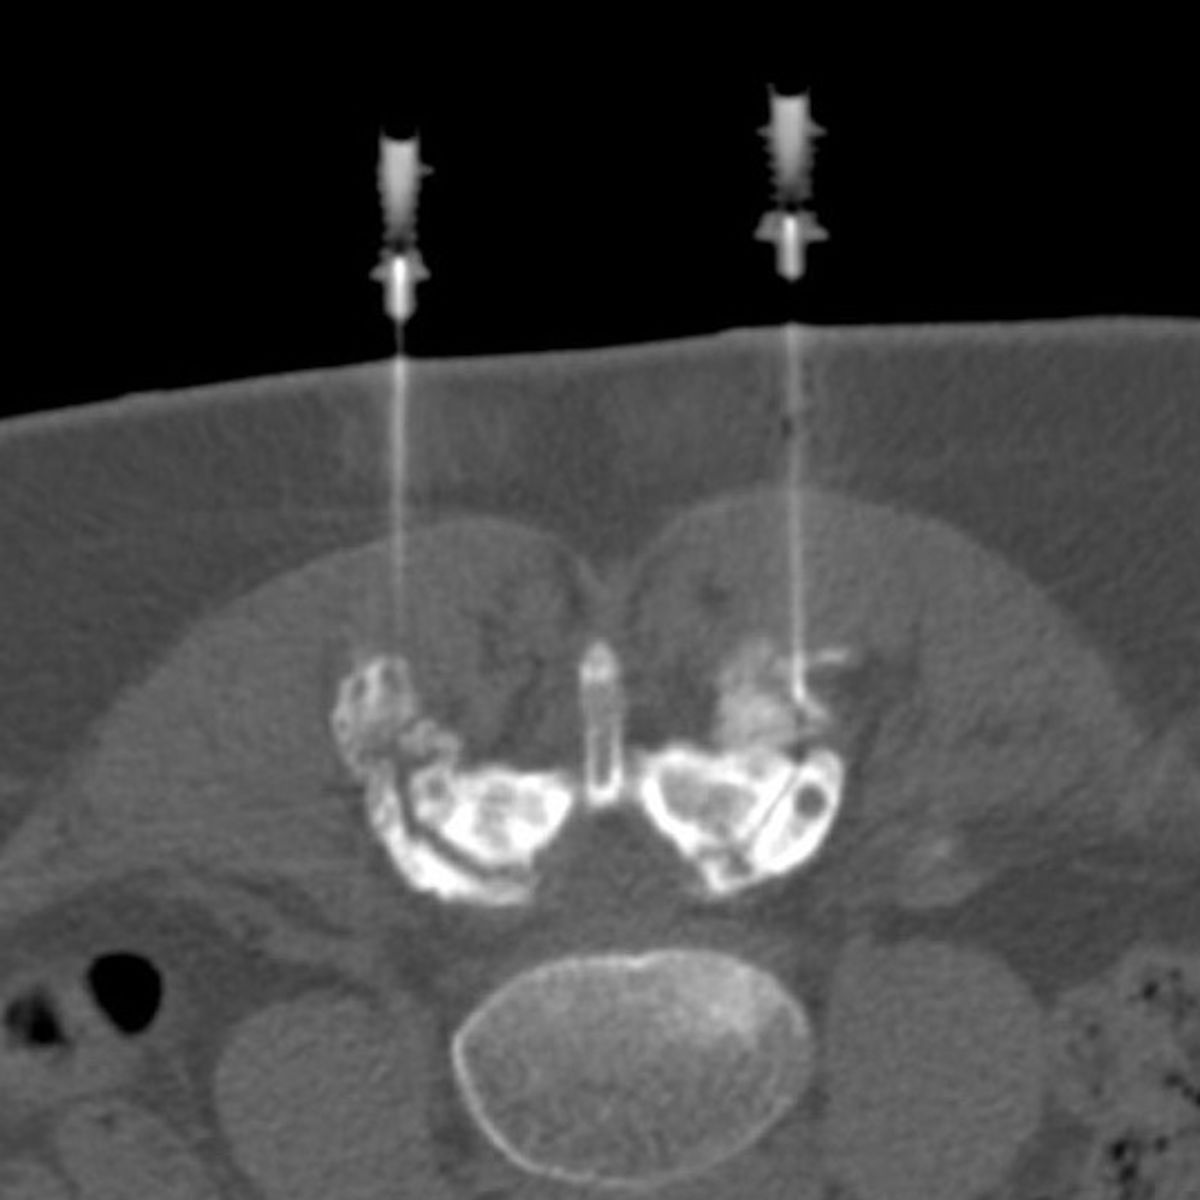

Zur Therapie stehen unsere modernen Großgeräte wie Computertomographen und Durchleuchtungsgeräte (Zwei-Ebenen-Angiographie) zur Verfügung, die schonendes und präzises Arbeiten im Millimeterbereich gewährleisten, was der Sicherheit und der Verbesserung der klinischen Ergebnisse für unsere PatientInnen dient.

- Minimalinvasive CT-gesteuerte Schmerztherapien